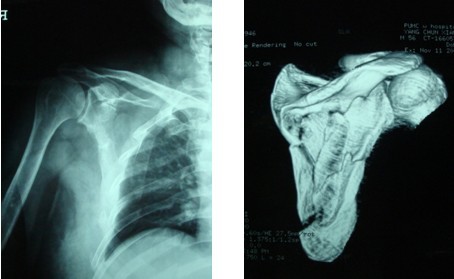

患者,男性,56岁, 因车祸伤致腰痛、胸痛、骨盆痛6小时来我院就诊。患者2009-11-8被汽车撞伤腰部,当时双下肢不能活动,伴头晕、大汗,无明显外出血,就诊于当地医院,查血压70/50mmHg,诊断为“多发伤,休克”,予抗休克治疗,X线和CT检查示“胸12椎体爆裂骨折、腰2-4右侧横突骨折(见图1、图2);右肩胛骨骨折(见图3、图4);多发肋骨骨折、右侧血胸(见图5);右耻骨上下支粉碎性骨折、右髂骨骨折合并右骶髂关节半脱位(见图6、图7)”。

图3、图4 X线片和CT三维重建示右肩胛骨骨折